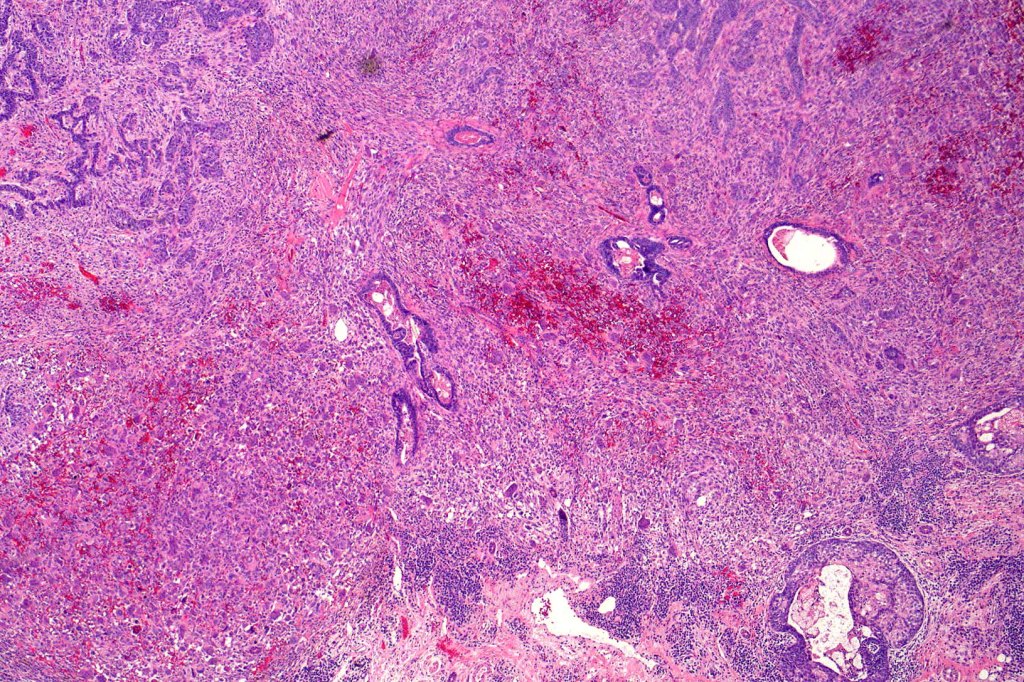

Carcinosarcoma

Cutaneous carcinosarcoma (metaplastic carcinoma, carcinoma with heterologous differentiation)

Histological features

•Osteoid

•Chondroid

•Smooth muscle

•MFH-like features with osteoclasts

•Neural differentiation